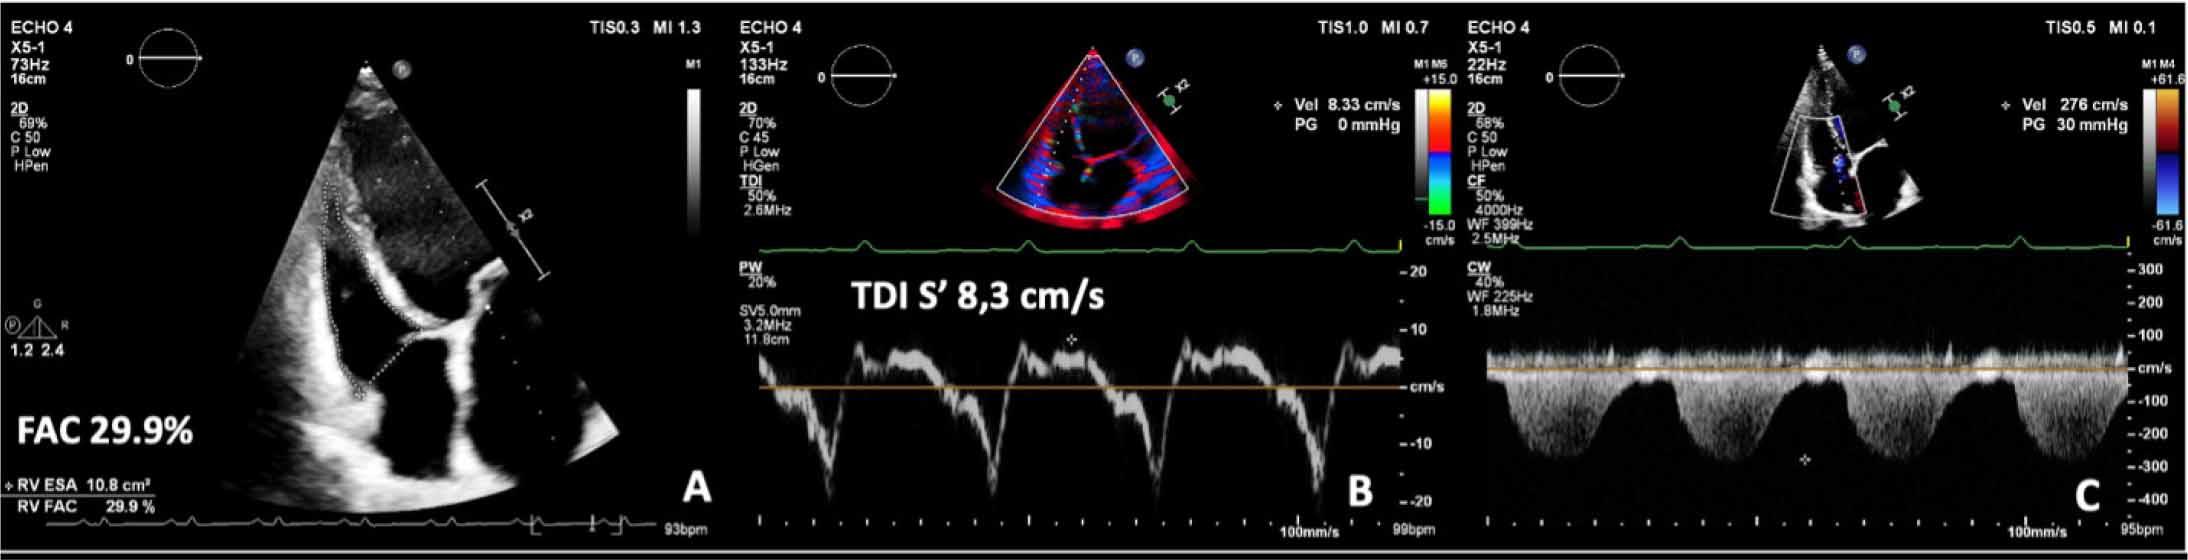

At presentation, transthoracic echocardiography showed dilated LV with severe diffuse hypokinesia of the walls, an estimated ejection fraction of 15% (Supplementary material online, Video 1), with severe mitral functional regurgitation. Additionally, she presented global and longitudinal RV systolic dysfunction, defined by a fractional area change (FAC) of 29% and a tricuspid annular systolic velocity of 8.3 cm/s, and also a moderate tricuspid regurgitation, with systolic pulmonary pressure estimated at 35 mmHg, which indicates a low probability for pulmonary hypertension (Figure 2).

Assessment of right ventricle function showing a fractional area change (FAC) estimation of 29.9% (A) and a tricuspid annular systolic velocity (S′) by tissue Doppler imaging (TDI) of 8,33 cm/s; a peak velocity of the tricuspid regurgitation envelope of 2,76 cm/s indicates a low probability for pulmonary hypertension (C).